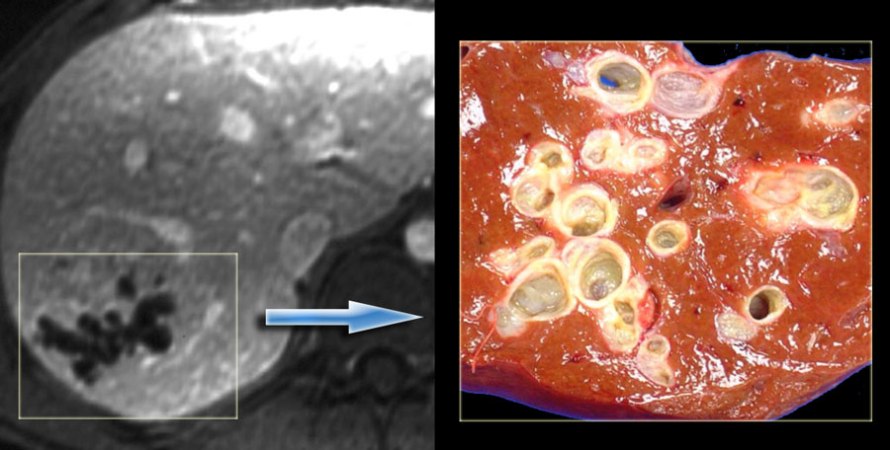

Tomografia (esquerda) e peça cirúrgica (direita) mostrando doença de Caroli bem delimitada.